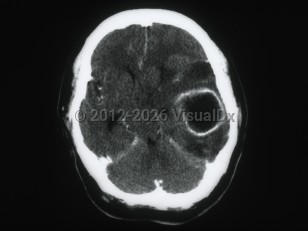

Brain abscess

Brain abscess is a focal intracerebral infection that begins with inflammation and progresses to a localized collection of pus. Bacteria, followed by fungi and parasites, most commonly cause it. Infection may be introduced hematogenously (bacteremia, fungemia), from contiguous areas (dental, sinus and ear infections, meningitis), via trauma, or by iatrogenic route (invasive neurosurgical procedures). In about 15% of cases, no source is identifiable.

Infection can be introduced via blood, from contiguous sites, or through trauma or surgery. Early cerebritis sets in following an inflammatory cell response (days 1-3), necrosis (days 4-9), and development of a collagen capsule (days 10-14).